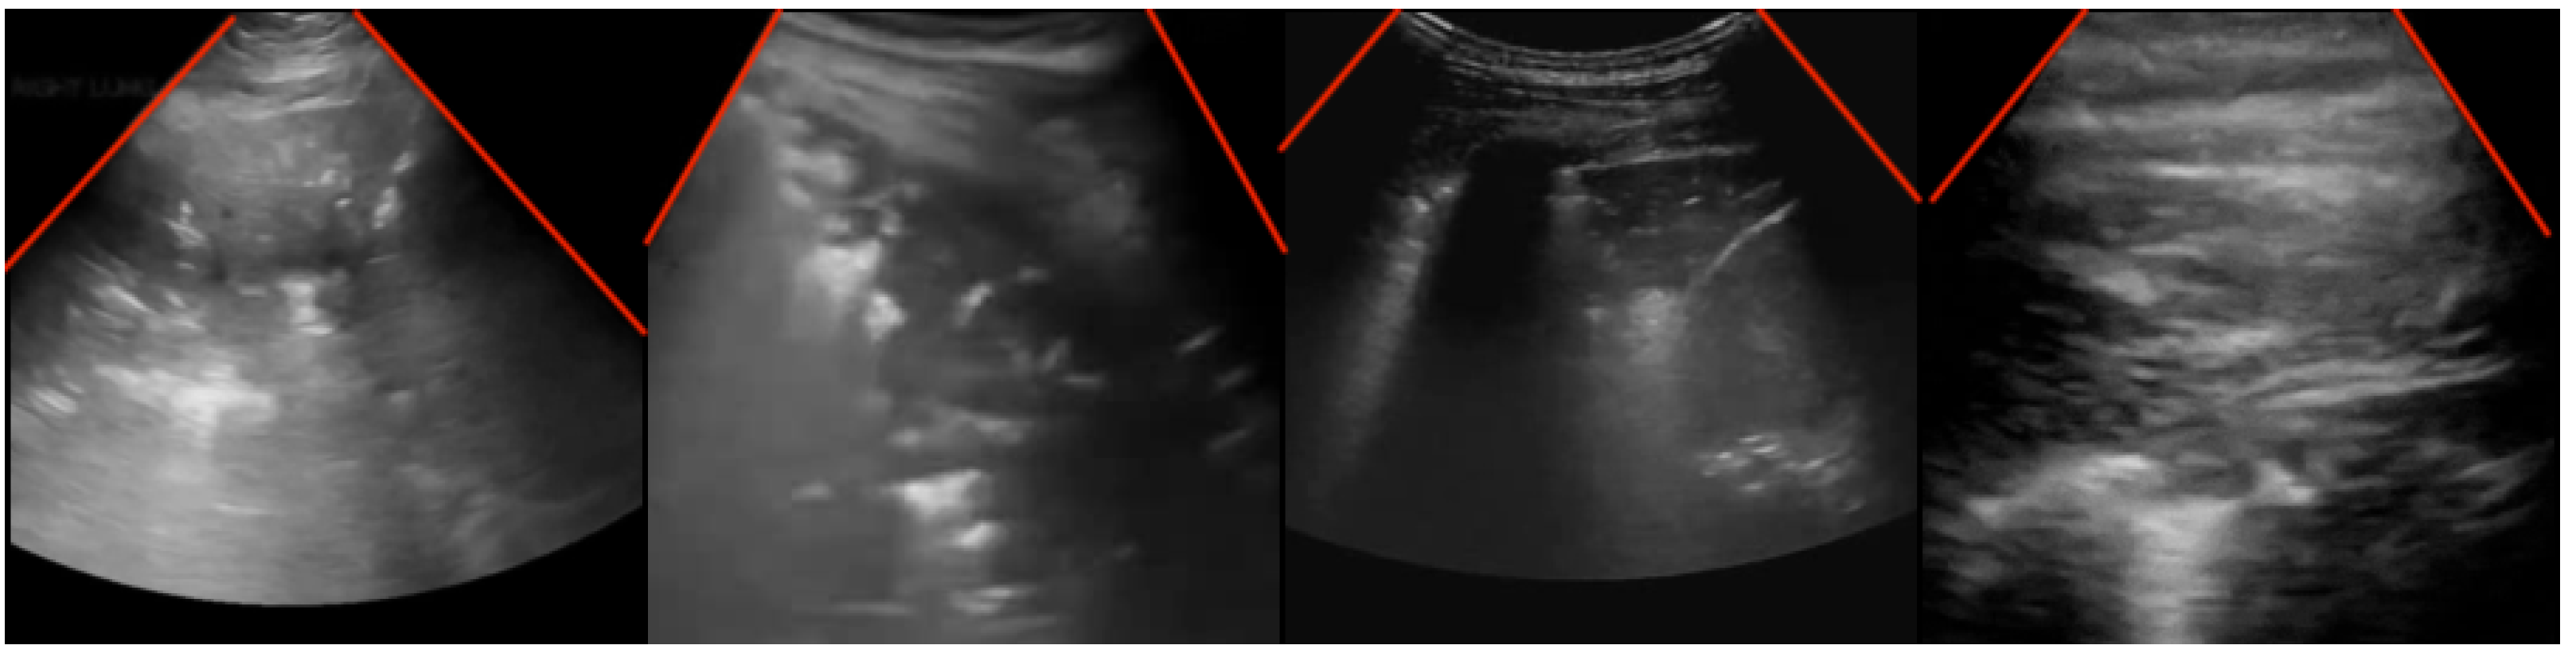

Table 2 compares the proposed approach against transforming the convex images through linear rectification. This approach, seen in Yaron et al. [30] takes the polar coordinates of convex probe images and transforms it into Cartesian coordinates. Different from the data augmentation approaches compared in Table 1, this existing approach is explicitly to aid in decreasing the heterogeneity between different probes. An example of a transformed image can be seen in Figure 6. The polar coordinates are sampled the same way as in the piecewise affine transform.

Figure 6. Sample ultrasound images, after linear rectification, as seen in Yaron et al. [30]. The original image is shown on top while the transformed image is shown on the bottom. An ideal example can be seen in (a). An example where the original viewing window is cut off to be flat on the bottom, causing the resultant transformed image to have a curved black outline on the bottom is shown in (b). Finally, (c) shows an example of how poorly labeled viewing window corners can result in a rotated final image.